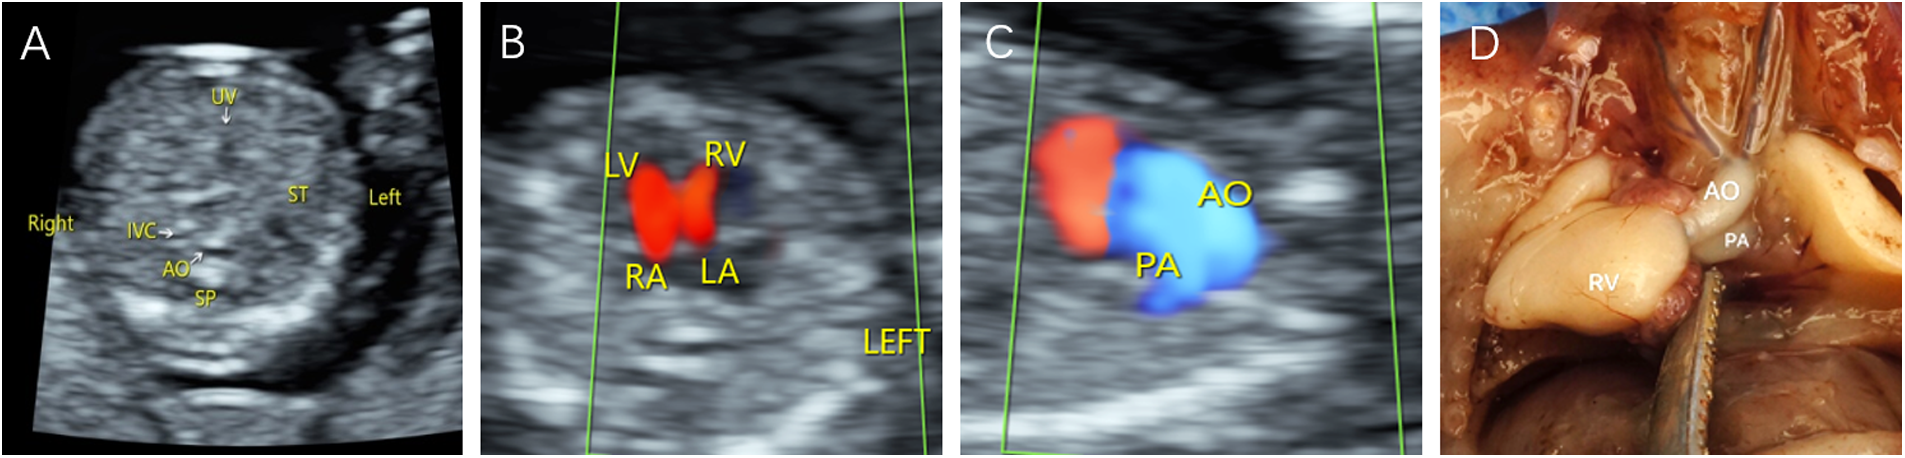

Figure 3

Fetal CC-TGA identified by echocardiography at 12 weeks and 6 days. (A) The inferior vena cava and descending aorta are located on the right side of the spine, and the gastric vesicle is on the left side. (B) The heart is located in the middle of the thoracic cavity with the apices facing right, and inconsistent atrioventricular connections are observed in the four-chamber view. (C) The aorta originates from the right ventricle, the pulmonary artery originates from the left ventricle, and the two great arteries are aligned in parallel. (D) Microscopic dissection of the heart: CC-TGA of the right heart.